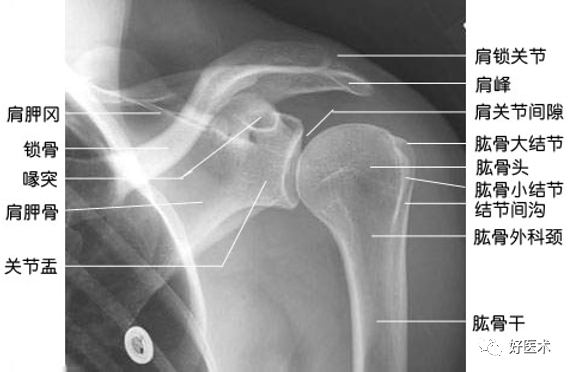

(1)正常肩关节X光正位片解剖

(2)肱骨近端解剖特点

-

肱骨头关节面呈半圆型

前外为大小两结节

大结节靠外,其下为大结节嵴

小结节居前,相当于肱骨头中心,下为小结节嵴

肱骨近端解剖(前面观)

1:解剖颈 3:大结节 5:肱骨头 6:结节间沟 8:小结节 10:外科颈

肱骨近端解剖(内侧面观)

1:解剖颈 5:肱骨头 8:小结节 10:外科颈